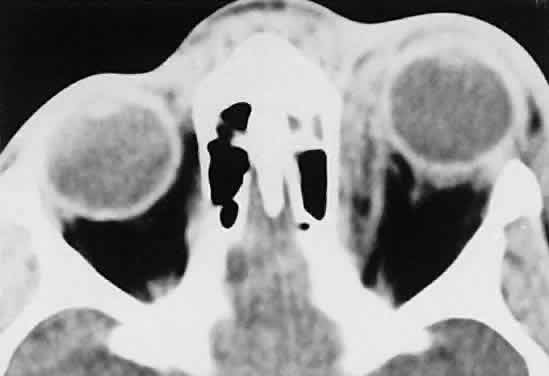

RHABDOMYOSARCOMA Rhabdomyosarcoma is the most common soft-tissue sarcoma in patients younger than 15 years of age and the most common primary orbital malignancy in childhood. These facts should not imply its frequent occurrence. Including all body sites, the annual incidence of childhood rhabdomyosarcoma in the United States is approximately 225 cases.2 The orbit is the site of origin in 5% to 25% of cases.3,4 However, site distribution varies with age. In children 5 to 9 years of age, for example, approximately 40% of primary rhabdomyosarcomas involve the orbit or eyelid.2 Although relatively rare, the tumor has a devastating natural history and demands a high index of suspicion in all cases of pediatric proptosis. Orbital rhabdomyosarcomas are slightly more common in females, with a 0.79 to 1 male-to-female ratio.2 The average age of presentation is 7.8 years, but the tumor may be present at birth and has been reported in patients as old as 78 years.5 A positive family history and associated anomalies have at times been identified, but these are exceptions rather than the rule. Classically, orbital rhabdomyosarcoma presents in an abrupt manner, with rapid progression of proptosis over days to weeks. A somewhat more indolent course does not exclude the diagnosis, however. Vigilance also should be exercised when rapidly expanding eyelid lesions are encountered. Rhabdomyosarcoma may present as ptosis or an eyelid mass rather than with proptosis.4 An eyelid rhabdomyosarcoma can occur as a congenital lesion.6 Within the orbit, rhabdomyosarcoma occurs most often, but not exclusively, in the superior nasal quadrant, with downward and outward displacement of the globe. CT scans show the topography of the orbital mass (Fig. 1A), as well as the possible extension into adjacent bone, paranasal sinuses, or the intracranial cavity. The circumscription that may be noted on CT is relative, because the lesion is not encapsulated and microscopically infiltrates normal tissue. Echography shows internal echoes of low-to-medium amplitude. Because the cellular tumor absorbs acoustic energy, the amplitude of the spikes falls off somewhat through the lesion (see Fig. 1B and C). MRI can help define the tumor's relationship to extraocular muscles (Fig. 2). The clinical diagnosis must be confirmed by biopsy. Because of the risk of seeding the biopsy tract, a transcranial approach should be avoided. If possible, the periosteum should not be violated because it presents a relative barrier to tumor invasion. Depending on its location, the lesion should be approached transconjunctivally or with an eyelid crease incision/transseptal dissection. The surgeon must balance the benefit of complete gross tumor resection with the risks of functional impairment and tumor dissemination that may accompany that effort. Tissue samples should be fixed in formaldehyde solution and glutaraldehyde for light and electron microscopic study. In addition, the value of immunohistochemical differentiation has been established for some time, and the potential uses of molecular genetic studies are rapidly emerging. Consequently, the procurement of fresh or frozen tissue, or both, has been given the highest priority by the Biopathology Discipline within the Intergroup Rhabdomyosarcoma Study Group (IRSG).2 These techniques can facilitate the diagnosis of poorly differentiated tumors, and they may refine diagnostic and prognostic classifications, identify candidate genes, and contribute to potential gene therapies. Since the inception of IRSG-I in 1972, the multicenter collaboration has enrolled the overwhelming majority of patients diagnosed with rhabdomyosarcoma in the United States and has contributed significantly to enhanced patient survival. Patients with orbital tumors had a 96% versus 83% failure-free survival in IRSG-IV compared with those in the IRSG-III.2 As of the year 2000, with the IRSG-V study underway, the overall (all primary sites) 5-year survival of children and adolescents with nonmetastatic and metastatic tumors was approaching 80%. This progress reflects advances in diagnostic imaging and multimodal treatment, including chemotherapy (e.g., agents, combinations, timing), radiation therapy (e.g., doses, fractionation, timing), and surgery (e.g., diagnostic biopsy, local staging, salvage procedures). Therapeutic protocols have evolved over the past 30 years, but they also have not been uniform at any given point in time. Rather, they have been tailored to the patient's level of risk, as determined by multiple prognostic factors (Table 3). The concept of “risk-appropriate therapy”7 recognizes, for example, that a 6-year-old child with an embryonal rhabdomyosarcoma confined to the orbit might do well with a relatively simple chemotherapy protocol, avoiding the late adverse effects of high-dose radiation. Conversely, an 18-year-old patient with an alveolar rhabdomyosarcoma arising in the retroperitoneum, with metastases at presentation, needs aggressive, complex chemotherapy and radiation, and may still do poorly. Prognostic factors considered by the multidisciplinary team include the presence of gross or microscopic residual tumor, and this determination currently is being redefined with molecular techniques that may show residual disease even without microscopic evidence2; whether tumor is confined to the anatomic site of origin or invades surrounding tissues; tumor size, with 5 cm considered a breakpoint; regional lymph node involvement; and distant metastasis. Body site plays a role, and the orbit is relatively favored. The age of the patient at diagnosis is a strong independent predictor of outcome.7 The current pathologic classification for childhood rhabdomyosarcomas by prognosis2 is as follows: